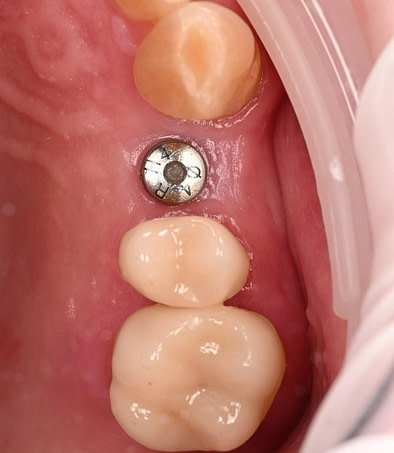

Three months after the implant surgery, a thorough post-operative assessment revealed excellent healing and implant stability.

Digital impressions were captured using the TRIOS 4 intraoral scanner, and the implant-supported crown was designed using 3Shape Design Studio.